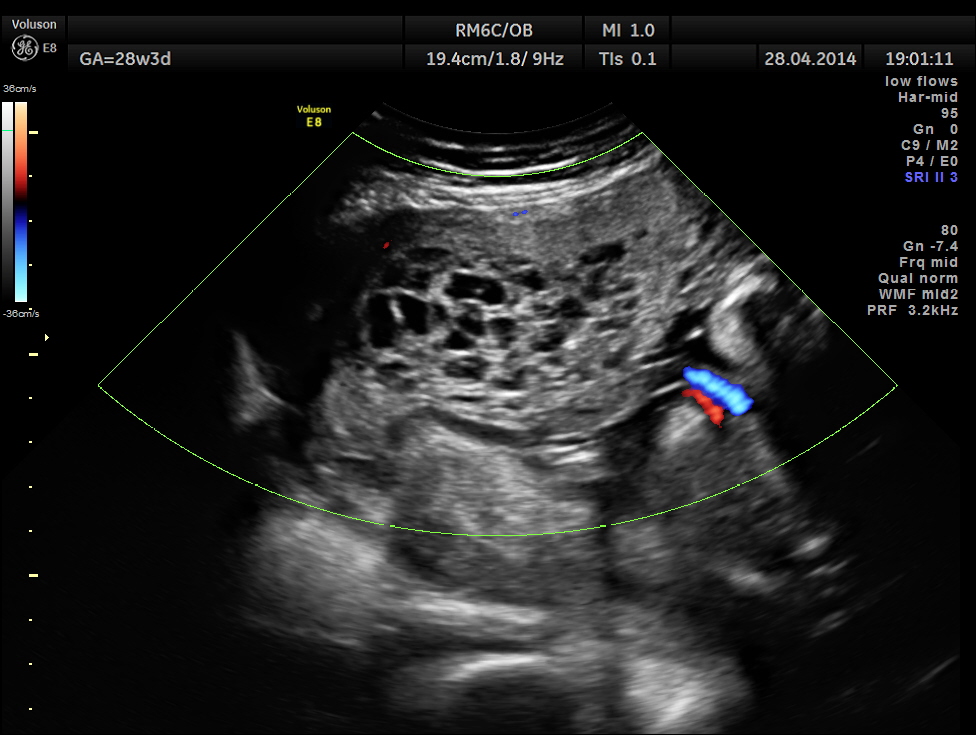

The patient was again seen after 2 months , when the findings were very similar.

She came again after 2 months .The placenta appeared nearly the same , but showed more vascularity.